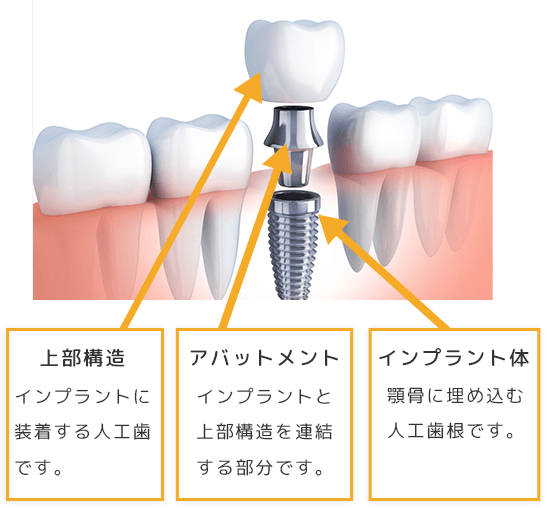

インプラントは、失われた歯の代わりに人工歯根を埋め込み、人工歯を装着して歯の機能を補う治療法です。

現存している健康な歯を削ることなく、天然歯のように自然な見た目で噛む力も同程度に回復することができます。

患者様のご要望をお伺いし、丁寧なカウンセリングを行います。

その後歯科用CTで撮影した3D画像を用いた精密診査を行い、検査結果を元に患者様のご希望にできるだけ沿える綿密な治療計画を立案します。

痛みを感じないよう局所麻酔を行い、埋入手術を行います。

その後、インプラントと骨が結合するまで約3~6か月程度の経過観察を行います。

むし歯や歯周病がある場合は治療を行い、症状が安定した状態になったら治療を進めます。

患者様に合った人工歯を作製し、骨とインプラントがしっかり結合したら、装着して治療は完了です。

インプラントを長持ちさせるためには、口腔内を常に清潔に保つことが大切です。 日々のお手入れに加え、定期的な検診を受けていただき、インプラントや人工歯の状態、咬み合わせ具合を確認し、メインテナンスを行う必要がございます。

| インプラント1本あたり | 220,000円~330,000円(税込) |